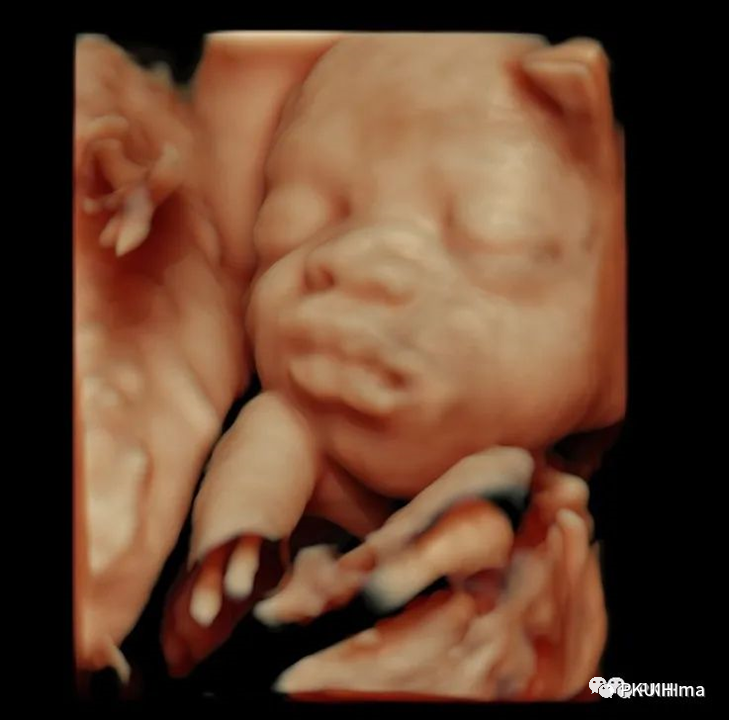

在思考或者是安静的休息